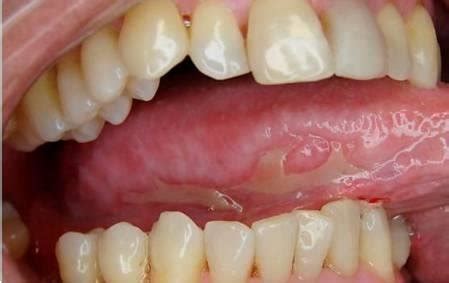

Las erosiones redondeadas suelen tener una etiología endógena (como las aftas) (fig. 12), las lesiones dentelladas son frecuentemente de origen exógeno (como traumatismos), mientras que las formas policíclicas apuntan más bien a una etiología vírica. En general, los tumores pediculados son benignos, mientras que un tumor sésil de base amplia suele ser maligno.

Figura 12. Las erosiones con una forma redondeada sugieren una causa endógena como en el caso de esta afta.